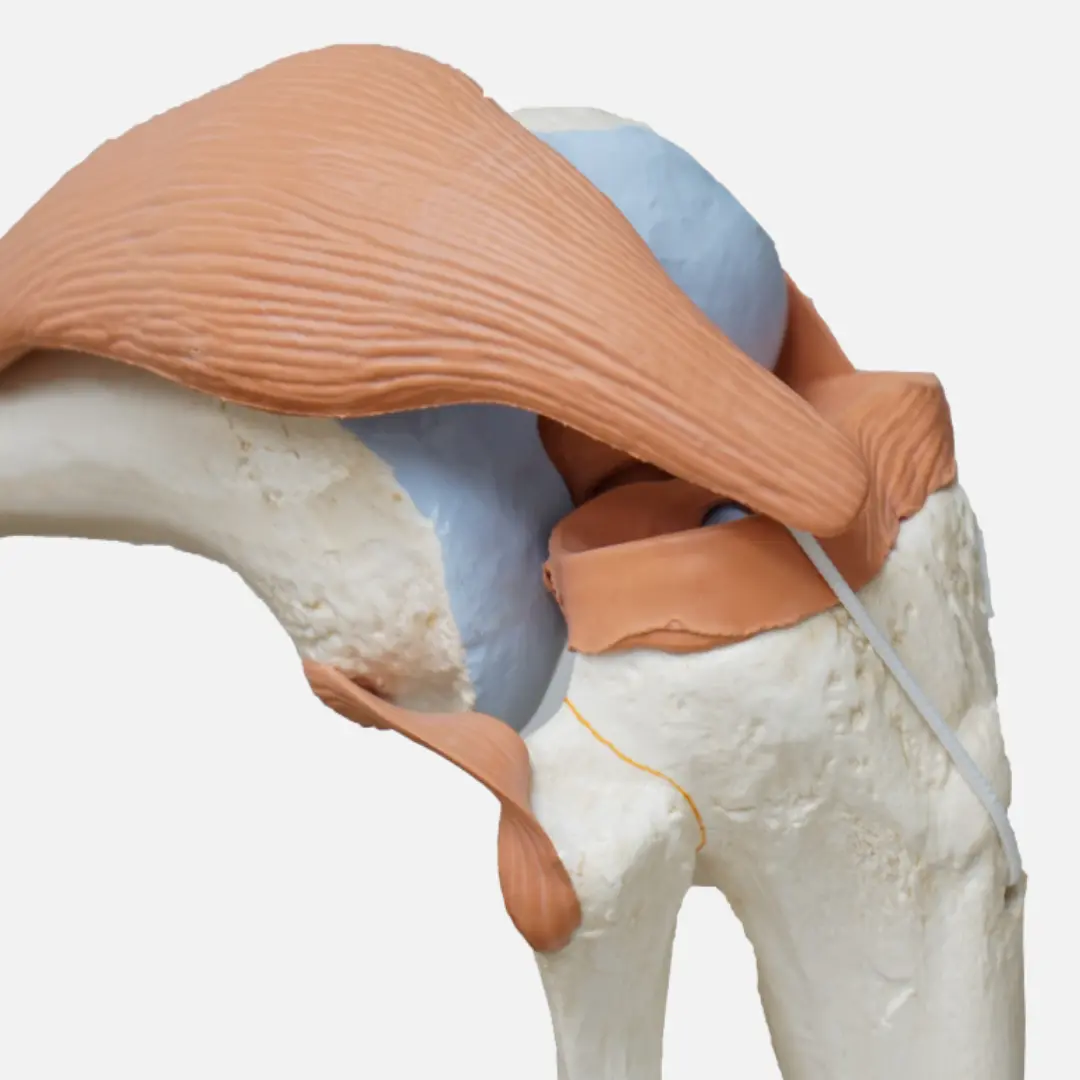

관절 건강에 대한 관심이 높아지면서 콘드로이친이 주목받고 있어요. 콘드로이친은 관절 연골의 주요 구성 성분으로, 관절 건강 유지에 필수적인 역할을 하죠. 콘드로이친 효능부터 건강하게 콘드로이친 복용하는 방법까지 정리해볼게요!

콘드로이친은 다양한 효능을 통해 관절 건강을 지켜줘요.

- 관절 연골 보호:

- 연골의 수분 보유 능력을 높여 연골이 마모되는 것을 막아줘요.

- 연골 세포의 생성과 유지를 도와 관절 기능 개선에 효과적입니다.